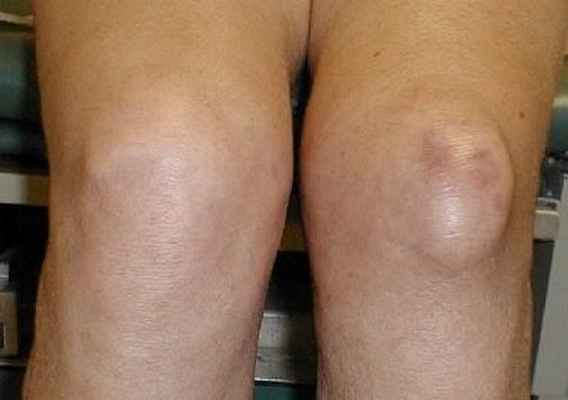

Препателлярный бурсит

Препателлярный бурсит — воспалительный процесс в синовиальной сумке, которая расположена между надколенником и покрывающей его кожей. Чаще всего это самостоятельное заболевание, развивающееся у лиц, профессия которых связана с частым стоянием на коленях (паркетчики, шахтеры и др.). При развитии бурсита спереди надколенника появляется малоболезненная большая опухоль с четкими границами.

Инфрапателлярный бурсит

Инфрапателлярный бурсит — воспаление поднадколенниковой сумки. При развитии бурсита ниже надколенника появляется отек и припухание.

«Колено домохозяйки» или препателлярный бурсит. Препателлярная сумка располагается между передней поверхностью надколенника и кожей, поэтому нередко травмируется при длительном стоянии на коленях. Клинически проявляется ограниченной, безболезненной и малоподвижной опухолью спереди от надколенника.

При значительных размерах бурсы возникает ограничение движений в коленном суставе, болезненность при максимальном сгибании колена. При других бурситах припухлость может располагаться ниже надколенника, по обе стороны связки надколенника.